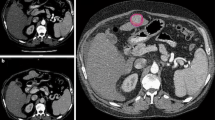

In patient 4, ill-defined and infiltrative perivascular mass formation (in the right upper anterior PVT) likely contributed to the variability. One observer (blue line) delineated a triangular zone of subtle arterial enhancement (nearly same as normal liver parenchyma) that was narrow medially and widened laterally adjacent to PVT on MRI (Fig. 2).